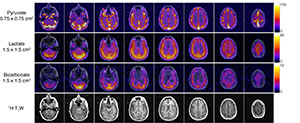

“We now acquire hyperpolarized metabolic MRI using varying resolutions between substrate (pyruvate, high signal) versus metabolic product (lactate/bicarb, limited),” says Dr. Larson. This enables visualization of smaller features that would otherwise be missed at coarser resolutions. Overall, this technique shows promise to improve future studies by maximizing metabolite SNR while minimizing partial-volume effects from the injected substrate.